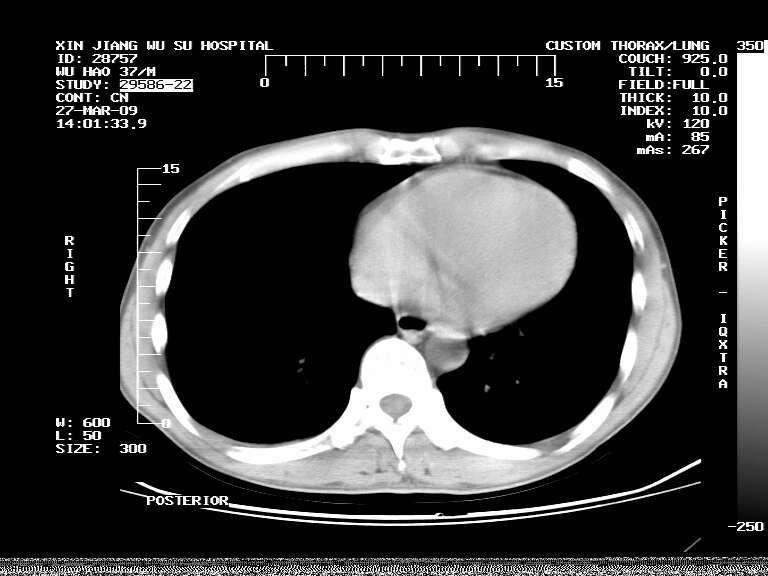

男,37岁,体检胸透发现阴影。

患者体检发现 无症状 左肺下叶占位,边缘模糊,可见血管聚束、分叶、胸膜牵拉,增强呈不均匀性强化。 首先考虑左肺下叶周围型肺癌,建议穿刺活检。

患者体检发现 无症状 左肺下叶占位,边缘模糊,可见血管聚束、分叶、胸膜牵拉,增强呈不均匀性强化。 首先考虑左肺下叶周围型肺癌,建议穿刺活检。支持!

左肺下叶见一结节病变,边缘欠清不光滑,与胸膜粘连且胸膜局限性增厚,注药后呈环形强化,动脉期壁呈明显点环状强化,静脉期壁强化减低,中心密度低无强化,灶周无明显的卫星灶和水肿区(晕征)---考虑周围性肺癌,不除外感染性病变,建议穿刺活检。